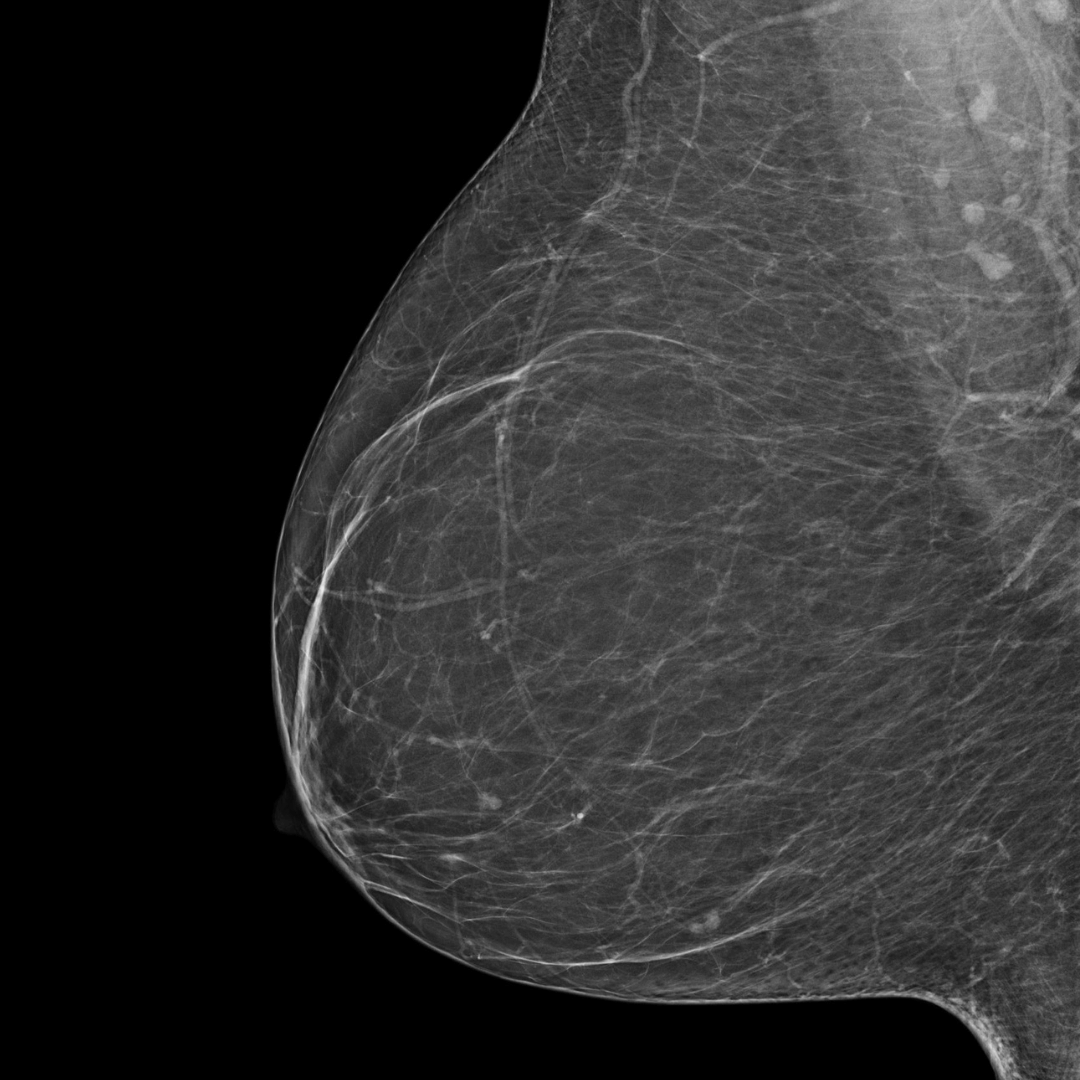

Category A

(least dense)

BI-RADS category A:

The breast tissue is almost entirely fatty and not dense.